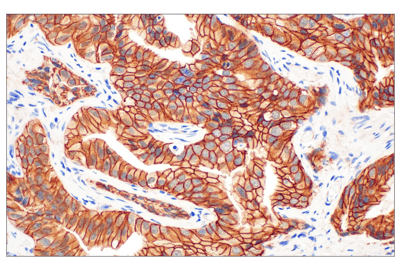

Immunohistochemical (IHC) analysis of paraffin-embedded human colon carcinoma using Phospho-Rb (Ser807/811) (D20B12) Rabbit Monoclonal Antibody #8516.